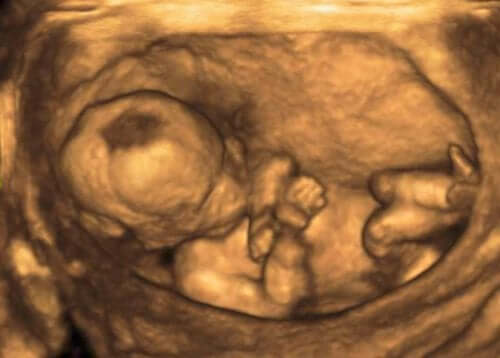

In genere, queste alterazioni si rilevano mediante la misurazione ecografica del volume del liquido amniotico. Questa misurazione si effettua mediante l’Indice di liquido amniotico AFI (dall’inglese Amniotic Fluid Index).

Per ottenere questi dati si divide l’utero in quattro quadranti e si misurano verticalmente in centimetri le aree libere del feto e del cordone ombelicale. Si considera un AFI normale una misurazione compresa tra gli otto e i ventuno centimetri.